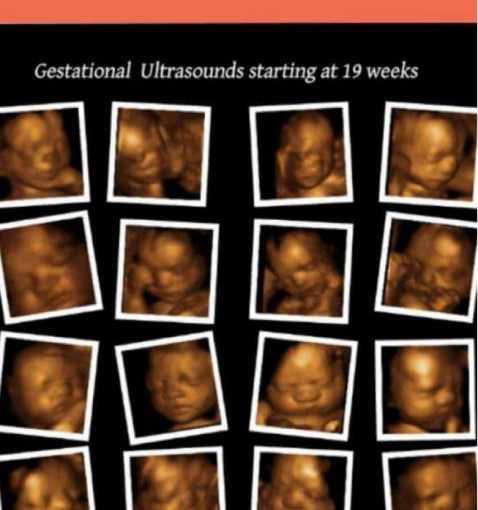

據多倫多星報報道,Pickering 一家診所BabyView使用3D Ultrasounds技術,讓準媽媽們看嬰兒的照片,但卻被數位母親揭發:所有不同母親嬰兒的臉都一模一樣。

許多使用過3D Ultrasounds服務的母親在臉書上放了自己嬰兒的照片,才發現所有嬰兒長得一模一樣,以致她們大怒。最先發現這個問題的母親是兩位來自奧沙華的母親,她們交流后決定在社交網上揭發這個騙局。至週三夜晚,已經有900人加入她們團體,有30人認為她們的BB照是假的。